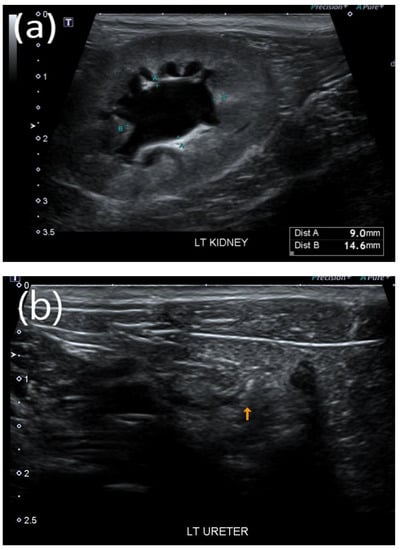

After surgical removal, the stone, which contained calcium oxalate, was confirmed to have a diameter of approximately 3 × 2 × 1 mm3. For cats in the stone passage success group, changes in the locations of the stones and improvement in the extent of renal pelvis dilatation owing to obstruction were observed on ultrasound (Figure 1a–d). In one case where bilateral ureteral stones resolved simultaneously, treatment was successfully terminated with a dramatic decrease in creatinine (Figure 2).

Figure 1.

Representative ultrasound image of successful stone passage in a cat. (a) Dilated renal pelvis owing to obstruction and (b) high-contrast material presumed to be a stone in the distal part of the ureter. (c,d) After tamsulosin therapy, improved renal pelvic dilation and successful stone passage were confirmed through ultrasound imaging.